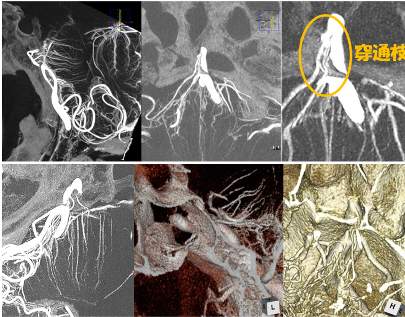

高分解能CBCTを用いた穿通枝描出テクニック